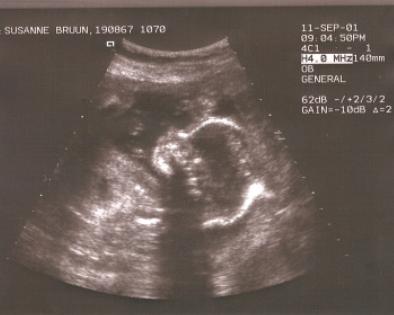

Scanning den 11. september 2001    indpakning